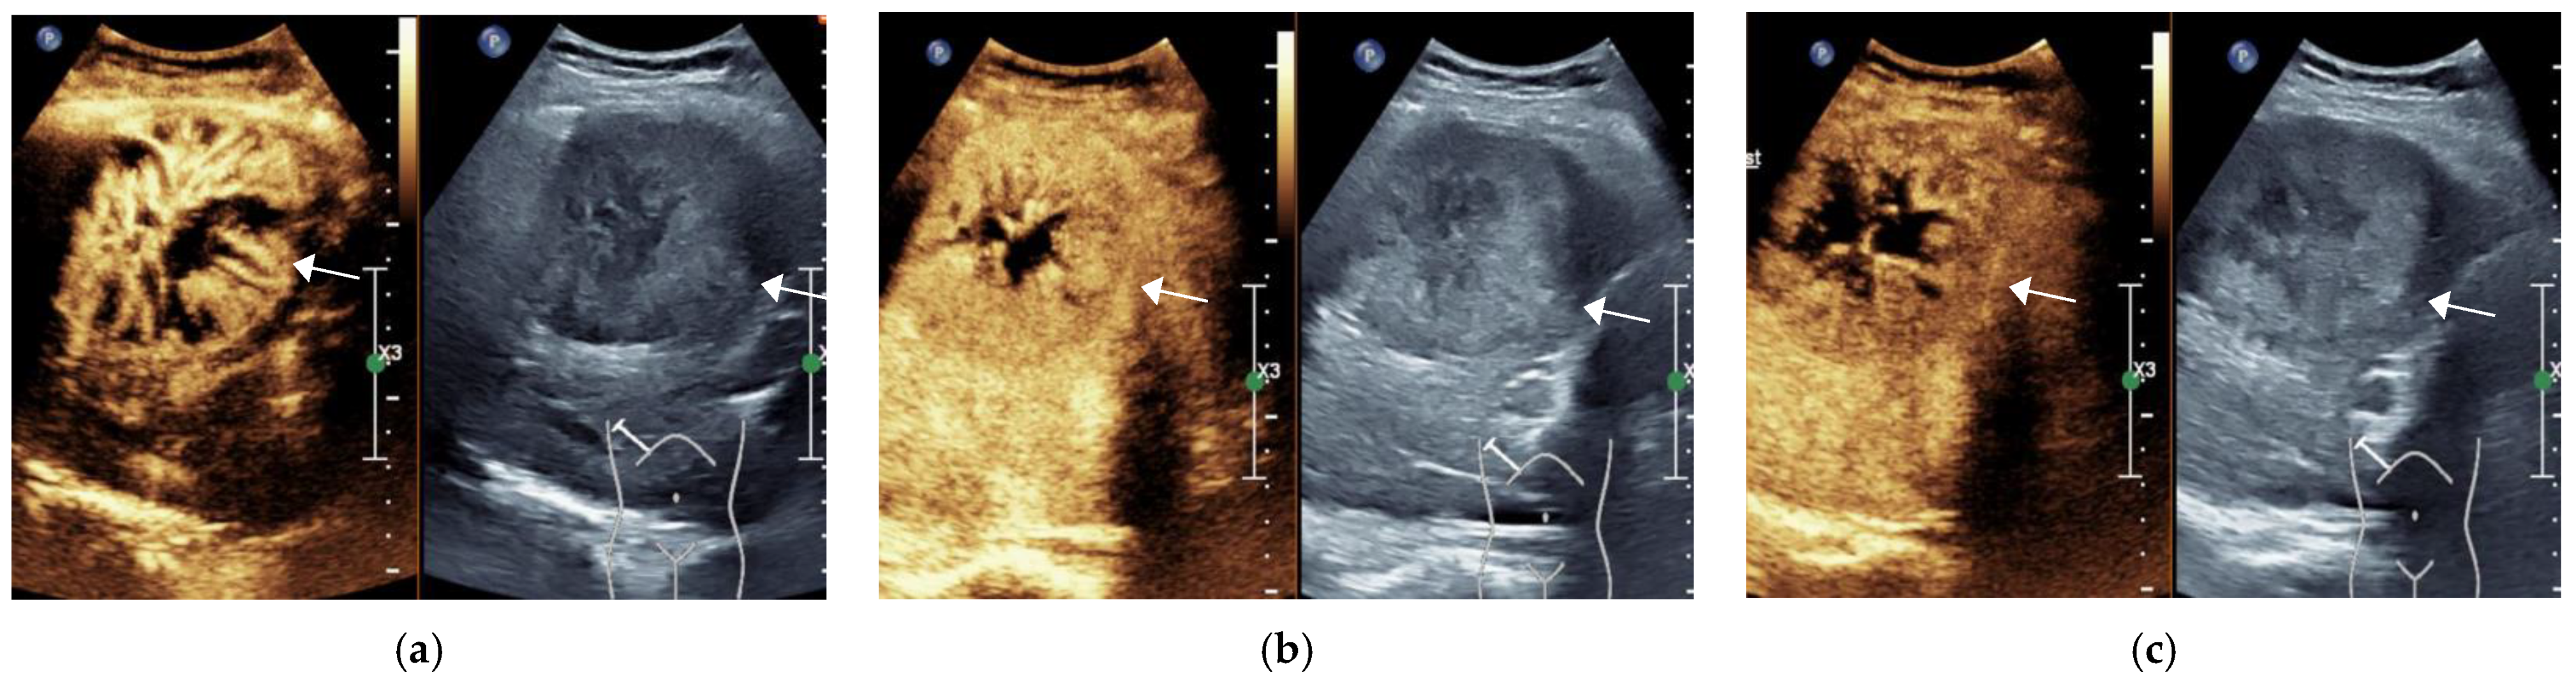

Figure 3.

Female, 73 years old, LR-M Category A hypoechoic lesion (arrow), approximately 6.8 × 6.6 cm in size, is seen in S5 of the liver, with peripheral irregular rim enhancement at 15 s in the arterial phase (a), starting to wash out at 34 s in the portal phase (b) and significantly wash out at 125 s in the delayed phase (c). The final pathological diagnosis was hypofractionated ICC.